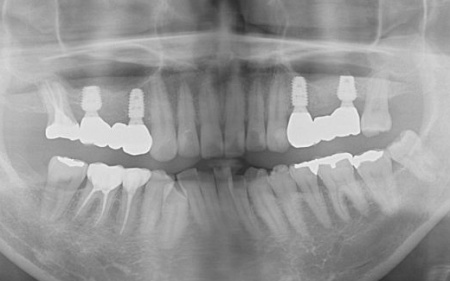

抜歯後は骨や歯茎の回復を待ち、口腔内の状態が安定した段階で、インプラント埋入手術へ進みました。

インプラントは、右上4番目と6番目の位置、左上4番目と6番目の位置に埋め込みます。

インプラントがしっかりと骨に定着したことを確認したら、精密な型取りを行い、ブリッジを作製して装着しました。

インプラント治療と併せて保存可能な歯の治療も進め、右上の一番奥の歯と右下の奥歯(前から5番目と6番目)に対して、細菌感染した神経を取り除いてから薬を詰める根管治療を行い、CAD/CAM冠という白い被せ物で修復しました。